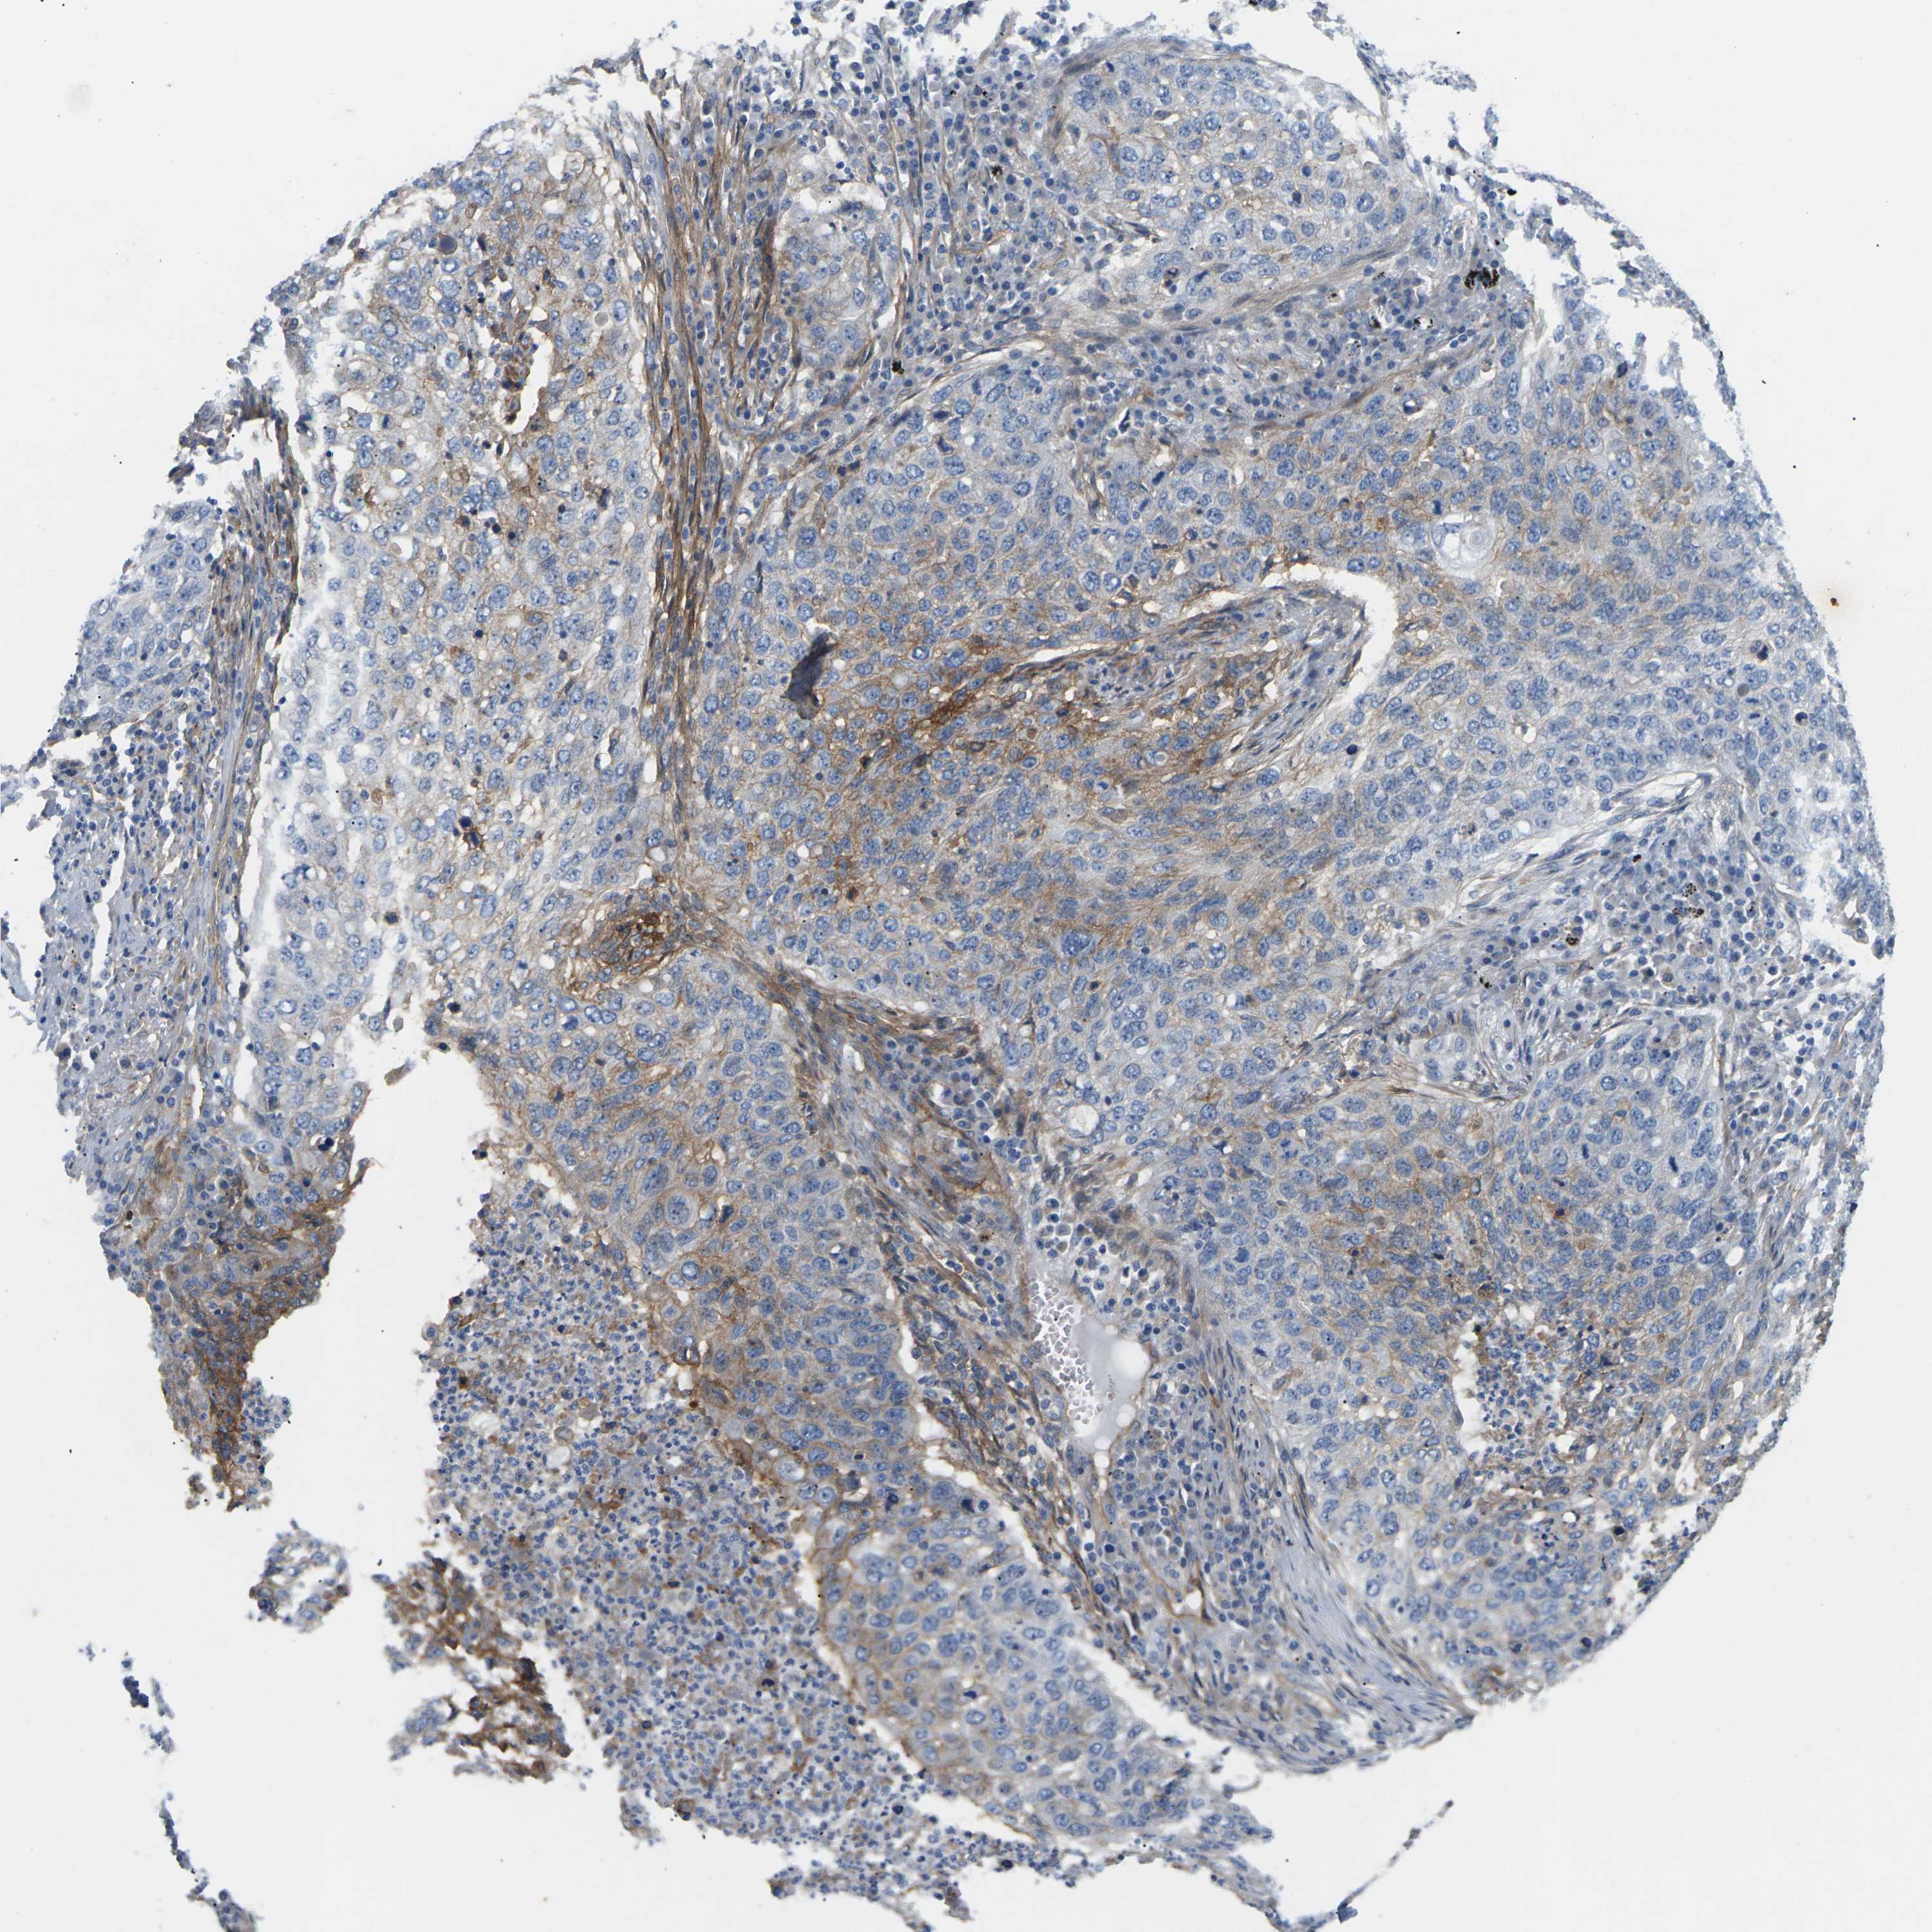

ITGA5 is potential prognostic, high expression is unfavorable in Lung Adenocarcinoma (validation)

Best expression cut offi

When clicking on this number, the vertical dashed line indicating cut-off, the interactive survival plot, and the Kaplan-Meier curve will be adjusted to show results based on the best expression cut-off.

: 40.8

P scorei

N/A

5-year survival highi

For melanoma and glioma, 3-year survival is shown.

5-year survival lowi

Average pTPM 44.9

Number of samples 105